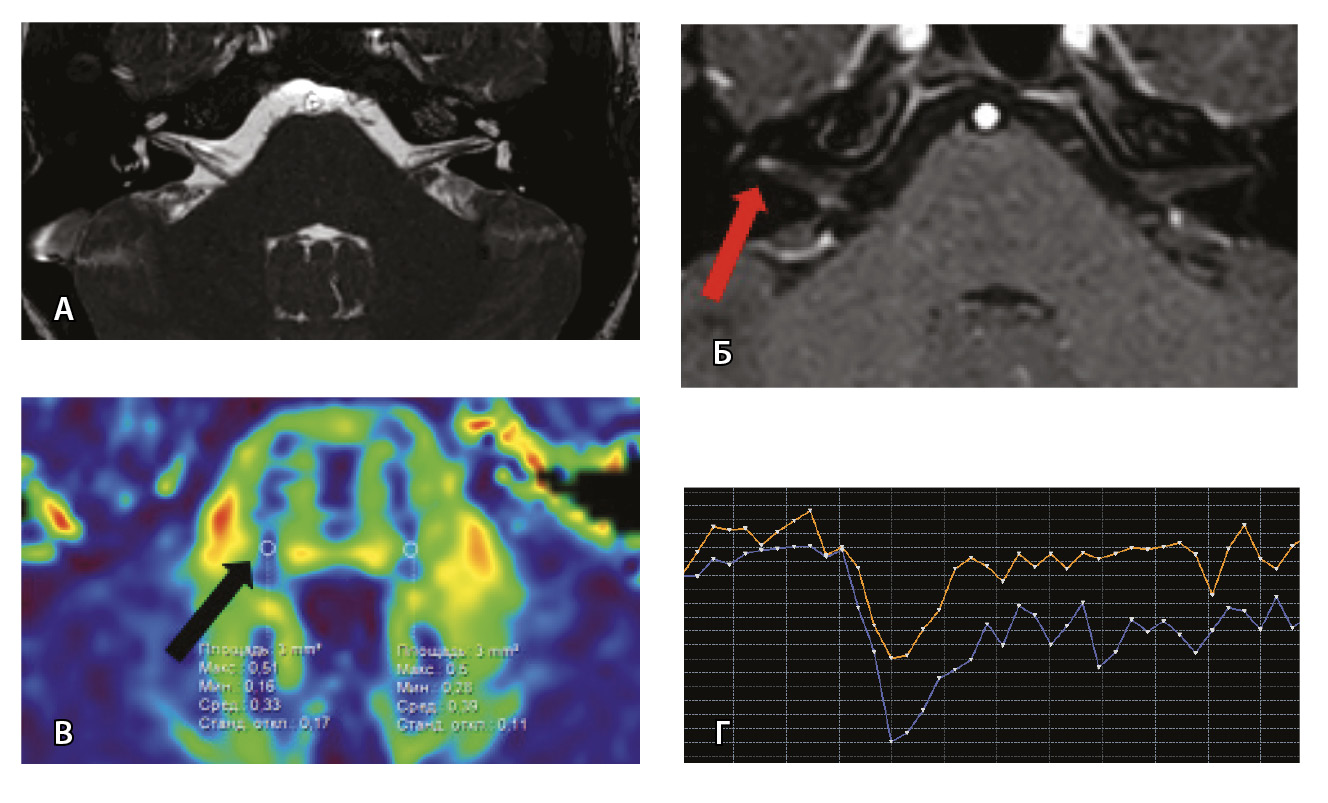

Рис. 6. Пациентка З. Магнитно-резонансная томография (МРТ) головного мозга: А – прицельная T2-SSFP на область мосто-мозжечкового угла; Б – Т1-взвешенное изображение с контрастным усилением; В – диффузионно-тензорная МРТ (фракционная анизотропия, ФА); Г – Т2*-перфузия. На изображении T2-SSFP патологические изменения на уровне прохождения лицевых нервов во внутренних слуховых проходах не определяются (А). При контрастировании отмечается накопление контрастного вещества правым лицевым нервом во внутреннем слуховом проходе (Б, красная стрелка). На уровне моторных ядер лицевого нерва в заднем отделе варолиевого моста на изображениях ФА на стороне поражения отмечается минимальное уменьшение показателя ФА до 0,33 (В, черная стрелка) и признаки гипоперфузии справа (Г, оранжевый график) по сравнению с контралатеральной стороной (Г, синий график). Данный пример демонстрирует типичные изменения при мультипараметрической МРТ у пациента с параличом Белла

Проведена МП-МРТ головного мозга и черепно-мозговых нервов. Заключение: МР-признаки локального участка повышенного накопления контрастного вещества правым ЛН во внутреннем слуховом проходе – изменения могут соответствовать невриту ЛН (рис. 6).